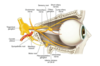

Descreva a via do reflexo fotomotor

Nervo óptico - Quiasma - Trato óptico - Núcleo pré-tectal - Núcleo de Edinger-Westphal - Nervo oculomotor - Gânglio ciliar - Nervos ciliares curtos

Onde ocorre a primeira sinapse da via do reflexo fotomotor?

Núcleo pré-tectal, localizado no colículo superior do Mesencéfalo

Onde ocorre a segunda sinapse da via do reflexo fotomotor?

No nucleo de Edinger-Westphal ou núcleo acessório do oculomotor

Onde ocorre a terceira e última sinapse da via do reflexo fotomotor?

No gânglio ciliar